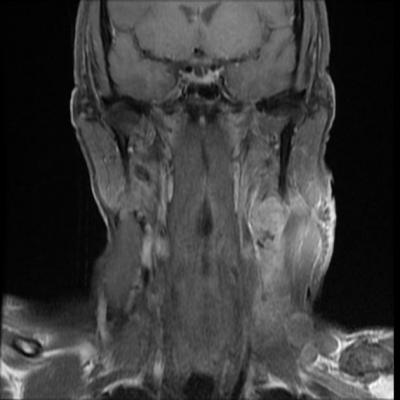

The investigators performed a comparative effectiveness analysis in patients with oropharyngeal squamous cell carcinoma (OPSCC), focusing on survival, side effects and costs. The study merged the HealthCore Integrated Research Database with state cancer registry data to identify 884 patients diagnosed with OPSCC from 2007 to 2014. The authors found no statistical differences between radiotherapy vs. surgery in overall survival, long-term gastrostomy dependence (stomach tube use), esophageal dilation or restriction, and bone toxicity effects. There was, however, an increase in acute gastrostomy use among radiotherapy patients who also received chemotherapy.

“While historical treatment outcomes for oropharyngeal cancer were quite poor, the combination of treatment innovations and more favorable tumor biology have resulted in three-year survival for over 75 percent of patients in this analysis,” said David Sher, M.D., associate professor of radiation oncology and of clinical sciences at UT Southwestern, and first author of this JAMA Otolaryngology study.